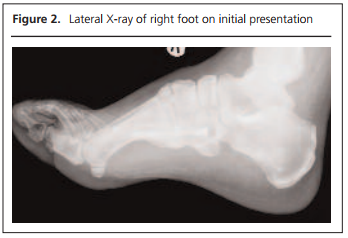

A 58-year-old Caucasian man with type 2 diabetes mellitus, obesity, hypertension, hypercholesterolaemia and previous left-sided Charcot neuro-osteoarthropathy presented to the multidisciplinary diabetic foot clinic at our University teaching hospital in September 2016. He had known secondary complications of diabetes including background retinopathy, peripheral neuropathy and erectile dysfunction. In addition, he had sustained fractures to both bases of the 5th metatarsals in 2013, which were stabilised with internal fixation. He had presented to the accident and emergency department three weeks previously with a swollen foot after having walked more than usual. There was pain in the plantar aspect of his foot with no visible wound. He had no recollection of any obvious injury. There was no temperature difference between the two feet. Foot radiographs did not show any new fractures or signs of Charcot neuro-osteoarthropathy. A deep vein thrombosis was excluded by ultrasound sonography. Within two weeks his symptoms had progressed, with erythema and oedema extending up to his mid-calf. His right foot became 2.5 degrees warmer than the left. His C-reactive protein (CRP) level was 107 mg/L (normal range 0–10) and his family doctor treated him with oral flucloxacillin for a presumed diagnosis of cellulitis. Although there was an initial improvement in his symptoms, the erythema, oedema and warmth did not improve despite his initial course of flucloxacillin and, later, teicoplanin (Figure 1). He was unable to put weight on his right foot. Repeat X-rays only highlighted the old fracture with no new changes compared to the X-ray performed a month previously (Figure 2). CRP had only fallen to 87 mg/L after antibiotic therapy. Due to slow resolution, a suspicion of gout affecting his midfoot was raised and Charcot neuro-osteoarthropathy was still considered a possible diagnosis. His urate level was noted to be raised at 439 μmol/L (normal range 200–430) in June 2016 and he was on bendroflumethiazide. Colchicine was therefore prescribed alongside his antibiotics. An MRI of his foot was requested. After a week there was some improvement in the oedema and he reported that the foot was less painful. However, the foot remained warm and the movement in his right foot was still restricted. His right foot was 3.5 degrees warmer than the left. His CRP had come down to 14 mg/L. One more week of teicoplanin was prescribed and he was initiated on prednisolone 30 mg once daily for one week alongside colchicine 500 μg twice daily after discussion with the rheumatology team. Following the course of prednisolone, there was continued improvement in his symptoms although his foot remained warm. He was given four weeks of colchicine 500 μg twice daily in total. When reviewed again a week later, the pain and swelling of his right foot and leg was settling and he had better movement in his right foot.

2017-11-Gohil_Figure_2